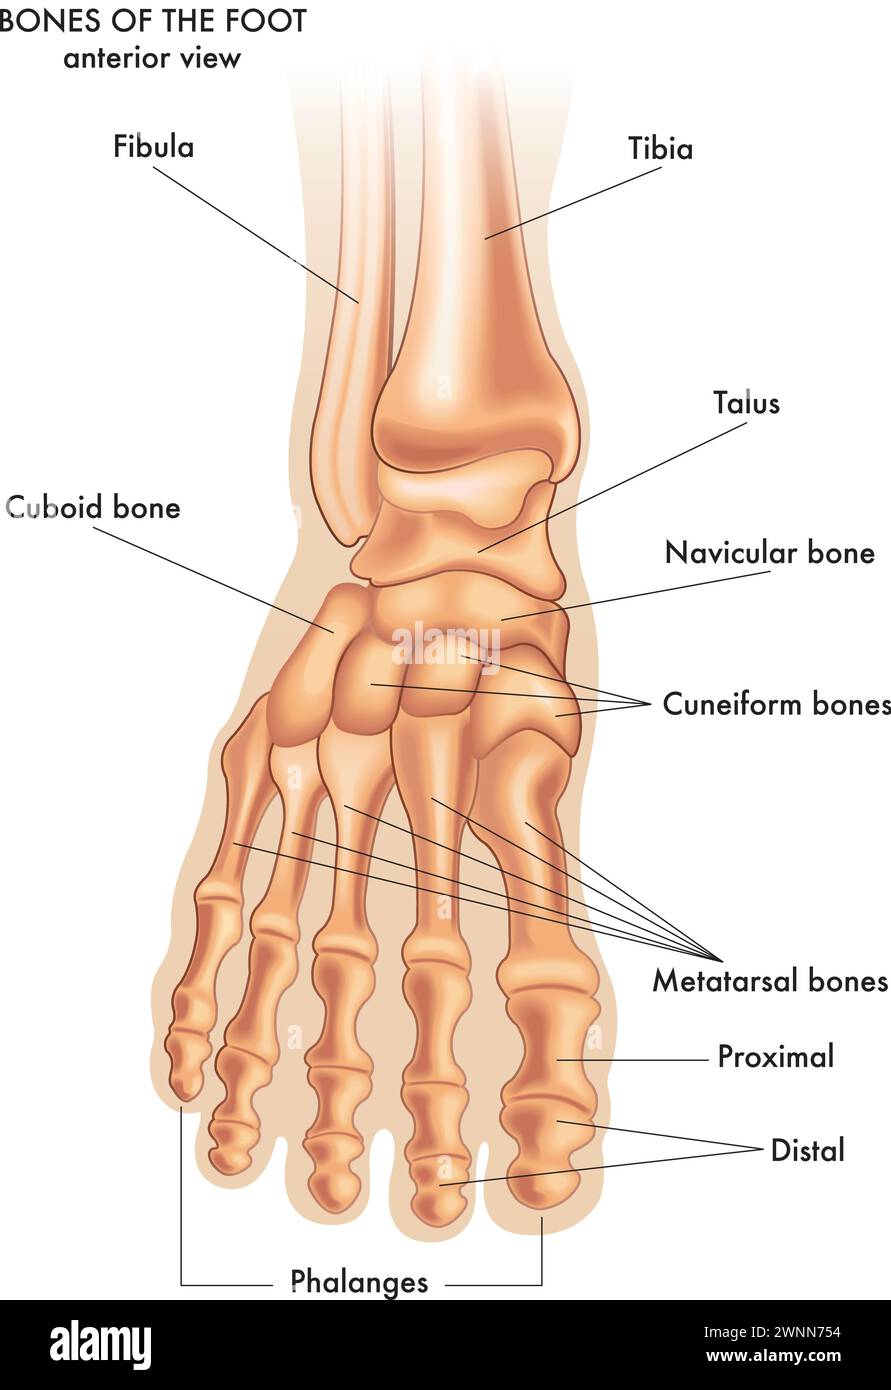

RF2WNN754–Illustration médicale des principales parties des os du pied en vue antérieure, avec annotations.

RF2WWY5XN–Os du pied humain avec le nom et la description de tous les sites. Vue supérieure. Anatomie humaine. Illustration vectorielle isolée sur un fond blanc.